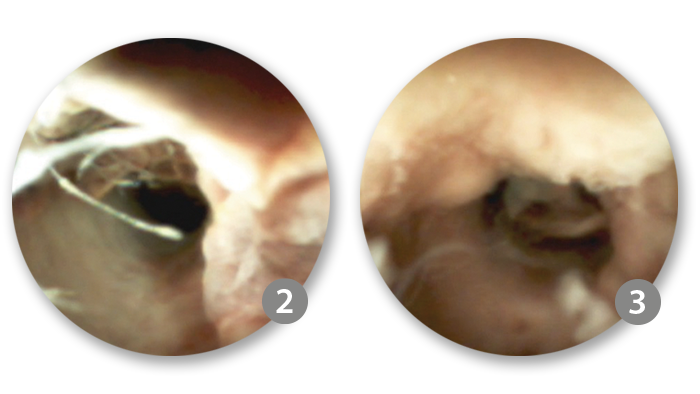

An ERCP with cholangioscopy using the SpyGlass™ DS System was conducted. ​

Following the removal of the plastic stent, the bile duct was re-cannulated using a Dreamtome™ RX. The initial cholangiogram reaffirmed the presence of a suspected malignant stricture, situated approximately 3-5 mm below the cystic duct take-off. Subsequently, the sphincterotomy was extended, and the SpyScope™ was meticulously inserted into the bile duct for direct visualisation.

The cholangioscopy with the SpyGlass™ DS System revealed normal left and right main hepatic ducts, along with the common hepatic duct.

However, a mass lesion with atypical villiform growth and increased vascularity was observed in the proximal-to-mid common bile duct (CBD). This growth, occupying 50-100% of the lumen, exhibited characteristic features consistent with cholangiocarcinoma.